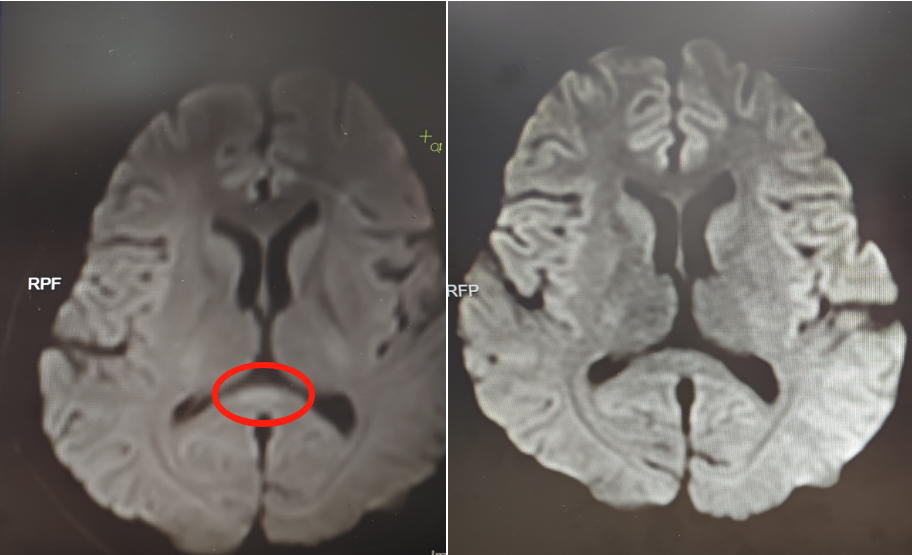

该院神经内六科主任胡运新接诊患者后,初步判断为脑炎。完善血清、脑脊液检测等,结果不支持颅内感染及自身免疫性脑炎,进一步完善细胞因子等炎症指标,结合核磁共振等,最终诊断患者为副感染性脑病。

▲治疗前(左)核磁共振提示胼胝体压部病变

副感染性脑病也称“第三类脑炎”,是一组急性脑病综合征,继发于系统性感染性疾病,如上呼吸道、肺部、消化道感染,在感染后1-3天即可出现症状。胡运新指出,该病的死亡率、致残率高,“早识别,早诊早治,多数轻症、及时就医的患者恢复较好,但延误治疗可能导致永久性脑损伤。”